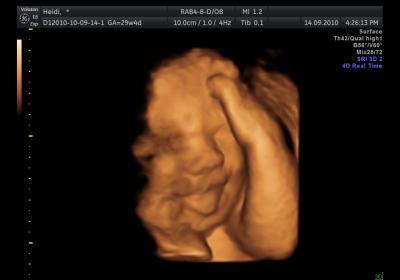

Hallo Mädels, hab gesehen hier wurde schon nach mir gefragt ... ... da bin ich wieder! Wie ihr ja wisst, hat unser Buzzerl einen schweren Herzfehler (HLHS). Mir und unserem Herzchen geht es sehr gut, es entwickelt sich alles sehr gut - aber es wird wohl ein sehr zahrtes Baby werden. Ich bin nach wie vor 14-tägig auf Kontrolle. Wir haben uns bereits alle Stationen im Krankenhaus angesehen, auf denen wir liegen werden und auch schon ein Zimmer für meinen Freund in der Nähe vom Krankenhaus reserviert. Wir müssen mit ca. 4-5 Wochen Krankenhausaufenthalt rechnen ... Die erste OP wird ca. am 4 Lebenstag sein. Operation am offenen Herzen. Angeschlossen an der Herz-Lungen-Maschine. Dauer: ca. 8 h Meinen nächsten Termin habe ich nächsten FR. Da werde ich dann den Termin für die Geburtseinleitung erfahren. Eingeleitet wird in der 38. SSW. ... schon in 6 Wochen!!! Was die Schwangerschaft betrifft, geht es mir sehr gut. Habe - gott sei dank - kaum Beschwerden ... oder zumindest keine Nennenswerten ... Ich genieße die Zeit zu Hause sehr! Treff mich mit Freunden, geh Einkaufen, relaxe und freu mich - so wie jeder andere hier - auf unser Baby! Kraft und Energie tanken tu ich wöchentlich bei meiner Kinesiologien. Das tut immer sehr sehr gut! Dauert 2 Stunden ... inkl. Ganzkörpermassage! Montags besuchen wir einen Geburtsvorbereitungskurs, da ja eine "normale" Geburt nicht ausgeschlossen ist. Also Kaiserschnitt ist nicht unbedingt notwendig, solang das Herzal vom Baby mittut ... Babysachen haben wir schon fast alles zusammen, und jetzt geht der Putzwahn los! Aber ich glaub das hat jeder ... Letzte Woche waren wir auf einen Herzkinder-Treffen. Dort haben wir viele Familien mit Herzkindern kennen gelernt. Konnten Erfahungen einholen und die Kinder sehen und mit ihnen reden. Man glaubt es kaum, aber wenn alle OP's gut gehen, merkt man kaum einen Unterschied zu einem gesunden Kind. *freu* Wir gehen mit der Situation sehr gut um. Geben unserem Buzzerl ganz viel Kraft und Energie für die OP's und glauben ganz fest daran, dass alles gut geht! Es muss einfach alles gut gehen ... Ich wünsch euch allen noch ein schönes Wochenende! Liebe Grüße Frühling

Bild zu Unser Herzchen ... Aktuelles von uns ... laaange! - Forum für November - Mamis

und hier noch ein 3D Bild